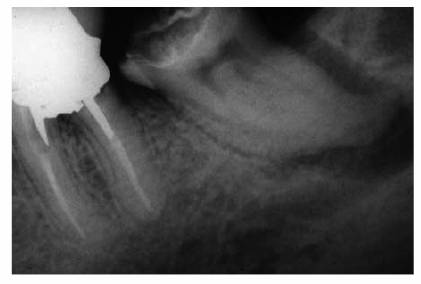

Figure 19-17A: Mandibular molar with a necrotic pulp. Root canal therapy was instituted.

Figure 19-17B: Ten years following completion of root canal therapy there is a complete bone fill-in. No periodontal treatments were performed on this tooth.